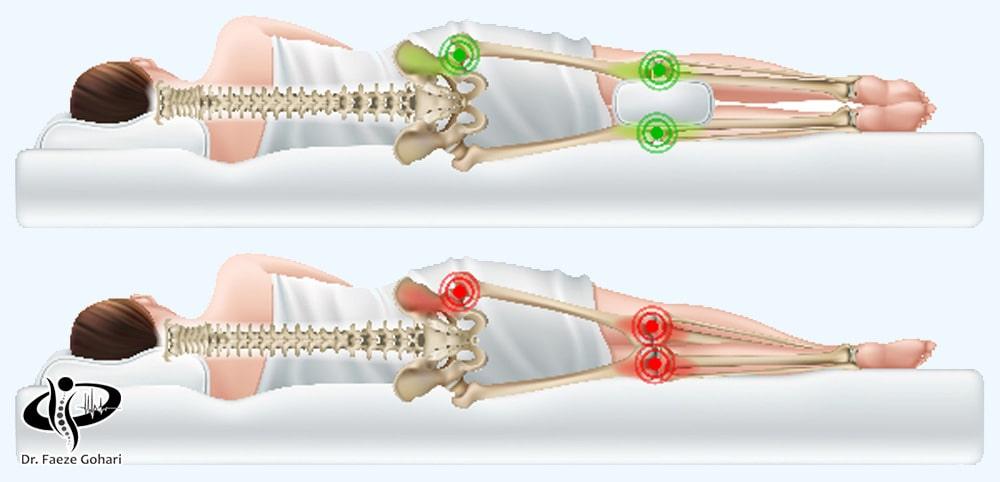

اقدامات 72 ساعت اول

بعد از تزریق سلولهای بنیادی و پیآرپی، باید تا 72 ساعت از استحمام و فشار به ناحیه تزریق خودداری کنید و بههیچوجه روی طرف آسیبدیده نخوابید. برای کاهش تورم و درد، استراحت کافی و استفاده از کمپرس سرد مفید است. همچنین باید از فعالیتهای سنگین اجتناب کنید و طبق توصیه پزشک داروها را مصرف کنید.